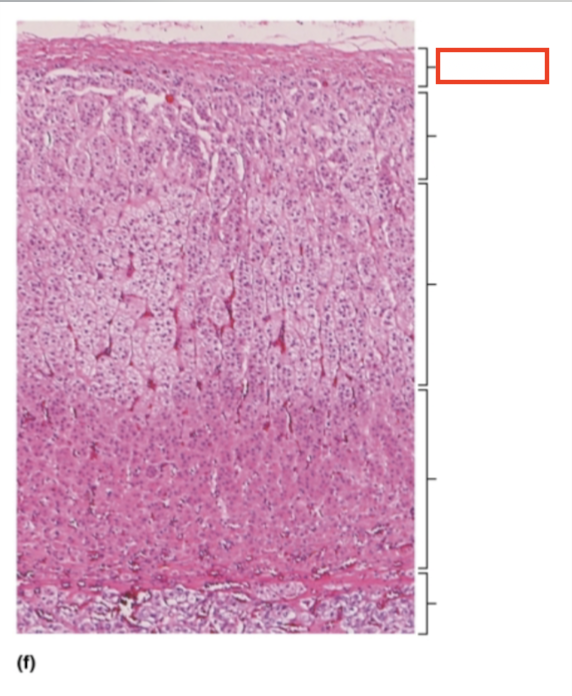

What structure is highlighted?

capsule

What structure is highlighted?

zona glomerulosa

What structure is highlighted?

zona fasciculata

What structure is highlighted?

zona reticularis

What structure is highlighted?

adrenal medulla

What tissue is shown?

adrenal gland

What hormones are produced in the zona glomerulosa of the adrenal cortex?

mineralocorticoids; mostly aldosterone

What hormones are produced in the zona fasciculata of the adrenal cortex?

glucocorticoids; mostly cortisol

What hormones are produced in the zona reticularis of the adrenal cortex?

gonadocorticoids; androgens (most are converted to testosterone and some to estrogen)

What are the target organs and effects of aldosterone?

kidneys; increases the reabsorption of sodium and water by the kidney tubules. increases the secretion of potassium in the urine

What are the target organs and effects of cortisol?

most body cells; promotes the breakdown of fat and protein, promotes stress resistance, inhibits the immune response

What are the target organs and effects of androgens?

bone, muscle, integument, and other tissues. in females, androgens contribute to body growth, contribute to development of pubic and axillary hair, and enhance sex drive. they have insignificant effects in males.

What hormones are produced by the adrenal medulla?

catecholamines; epinephrine and norepinephrine

What are the target organs and effects of catecholamines (epinephrine and norepinephrine)?

most body cells; mimics sympathetic nervous system activation, fight-or-flight response.